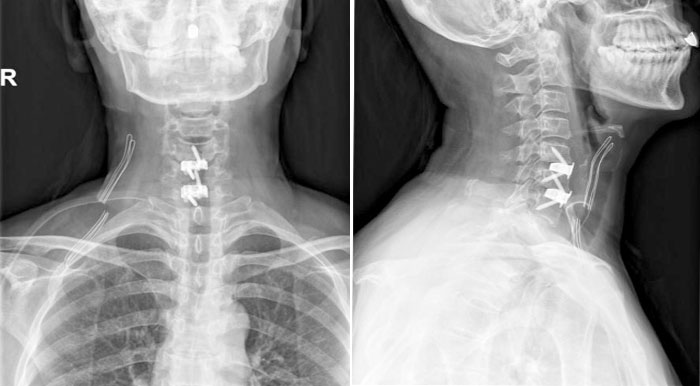

【胸科故事】辗转求医终有“医”靠…

近日,一位年轻患者在经历一个月内辗转多家北京知名医院却始终未能明确诊疗方案后,最终在北京胸科医院胸外科成功接受手术治疗,顺利康复出院。这一病例不仅为患者解除了“定时炸弹”般的健康隐患,也再次…